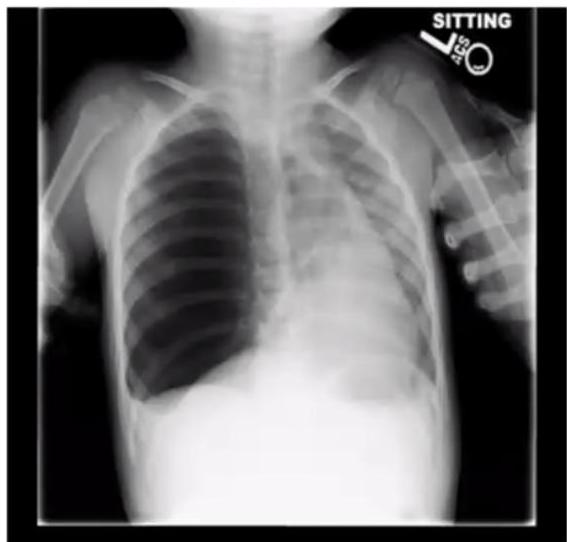

| Condition | Description |

|---|---|

| TGA (Transposition of Great Arteries) | Egg on side, generalized cardiomegaly, narrow mediastinum |

| VSD/AVSD | Cardiomegaly, increased pulmonary vascular markings (plethoric lung fields) |

| Ebstein Anomaly | Marked cardiomegaly extends wall to wall (Box Shape) |

| Tetralogy of Fallot | Boot shape heart with upward cardiac apex (RVH), concave PA segment, decreased pulmonary vascular markings |

| Total Anomalous Pulmonary Venous Drainage | Snowman or figure of 8 - dilated vertical vein on left + brachiocephalic vein on top + SVC on right form the head; enlarged atrium forms the body |

| Heart Failure | Nonspecific cardiomegaly |

TGA:

- Egg on string appearance - EGG ON SIDE, generalized cardiomegaly, Narrow mediastinum Description: Knee chest position (Squating position) to treat the episodes of TOF

Tetralogy of Fallot:

Description: Boot shape heart with upward cardiac apex due to Right ventricular hypertrophy and concave pulmonary artery segment and decrease pulmonary vascular marking at peripheral lung felid.

Dx: Tetralogy of Fallot

VSD/AVSD:

Description: cardiomegaly, increase pulmonary vascular markings (plethoric lung fields)

DDx : VSD, AVSD

Cardiomegaly (Heart Failure): (nonspecific)

Heart Failure with Pulmonary Edema:

Scenario: 3-month-old with heart failure, cyanotic and cardiac murmur

Findings:

- Small heart

- Pulmonary edema